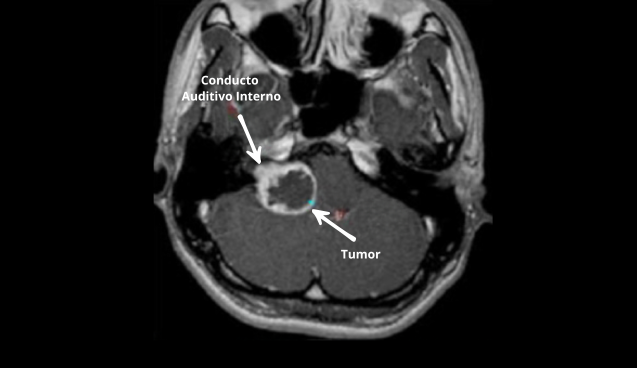

Neurinoma del acústico, tumores auditivos

Estrategias de abordaje de tumores que afectan la audición